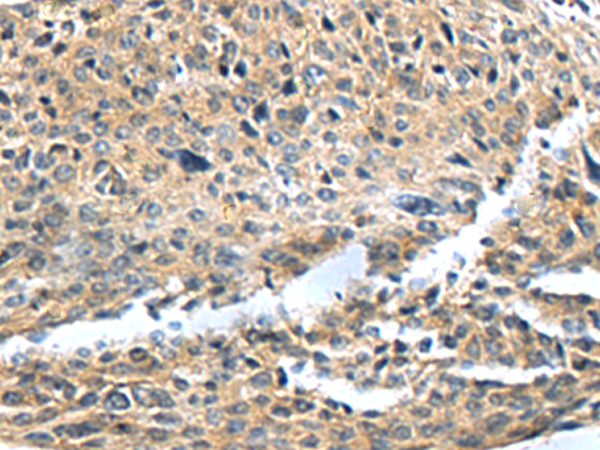

IHC positive control:

Human cervical cancer and Human colorectal cancer

IHC Recommend dilution:

50-100